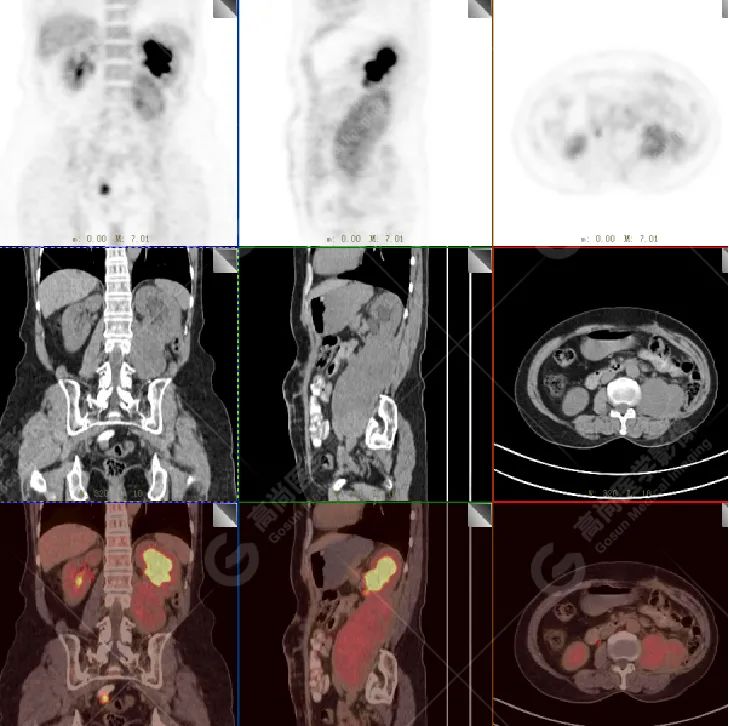

影像所见:左腹膜后间隙(原术区)见一长椭圆形软组织密度肿块影,范围约 8.0 cm×6.6 cm×15.8 cm,CT 值 30 Hu,FDG 高摄取,SUVmax5.0,考虑肿瘤复发,侵犯相邻左侧输尿管、腰大肌、后腹壁。

增强扫描肿瘤不均性中度强化,动、静脉期 CT 值:41 Hu、72 Hu(平扫 CT 值 30 Hu)。

PET 表现:FDG 高摄取。

PET/CT 检查可以全面了解肿瘤病灶范围,周围组织结构有无侵犯累及,其他部位有无转移。